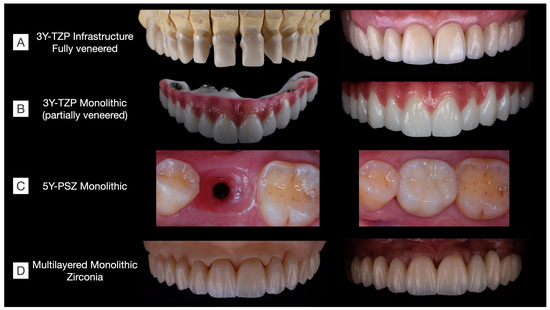

As discussed in the previous sections, the trade-off between optical and mechanical properties is challenging in the development of zirconia materials. Considering clinical indications, there is currently no commercially available material that is strong, esthetic, and hydrothermally stable for the manufacture of long-span prostheses. In brief, the following issues have been temporally reported: (1) veneered 3Y-TZP present a high risk for porcelain chipping [3,9,27,55]; (2) monolithic 3Y-TZP is opaque and prone to low-temperature degradation [59], with no clinical studies to confirm its survival in the long term; (3) 4Y-PSZ is recommended for up to three-unit FDPs [35]; (4) 5Y-PSZ is not recommended for FDPs in the posterior area nor for long-span FDPs [15]; (5) multichromatic systems present the same concerns that monolithic 3Y-TZP and 4Y- and ≥5Y-PSZs; and (6) novel multilayered zirconias appear an interesting option with the combination of the advantageous properties of zirconias that have a gradient structure provided by the different amounts of stabilizers in each layer [45]. While esthetic outcomes can be achieved through the laboratorial staining of multilayered systems (Figure 9), clinical studies are warranted to evaluate their long-term clinical performance.

Figure 9. Clinical cases rehabilitated with different kinds of zirconias. (A) 3Y-TZP infrastructures fully veneered with feldespathic ceramic in a tooth-supported upper arch rehabilitation including single-crown and three-unit fixed dental prostheses (Clinical case conducted by Benalcázar-Jalkh EB, and Pegoraro LF, and Dental Technician M. Portaluppi). (B) Partially veneered monolithic zirconia used for full-arch implant-supported prosthesis. The buccal aspect of the teeth and gingiva were veneered to achieve esthetic results, while occlusal and palatal aspects were designed in monolithic zirconia to reduce the risk of porcelain chipping (Clinical case conducted by Laura Firmo de Carvalho and Dental Technician Marcos Celestrino). (C) 5Y-PSZ, or “ultra-translucent” zirconia, was used to manufacture an implant-supported single crown over a Ti-base abutment (Clinical case conducted by Raphaelle SM de Sousa and Dental Technician/DDS Ricardo Tanaka). (D) Full-arch tooth-supported prosthesis manufactured in a monolithic multilayered zirconia (3Y-TZP/5Y-PSZ) and stained to achieve esthetic results (Clinical case conducted by Benalcázar-Jalkh EB, Bonfante EA, and Dental Technician M. Celestrino).

Oral rehabilitation necessitates the careful selection of restorative materials tailored to each clinical situation. In Figure 9, various clinical cases are depicted, each rehabilitated using different families of zirconias. Among the monolithic alternatives to fully veneered 3Y-TZP, the partially veneering of translucent 3Y-TZP has been proposed to mitigate the risk of porcelain chipping. However, concerns persist regarding the metastability of monolithic 3Y-TZP, particularly in unveneered and occlusal areas, where t-m phase transformation, along with surface crushing and grain pull-out due to tribological stress, are expected, though their long-term effects on prosthesis performance remain uncertain [58]. Furthermore, laboratorial-colored 5Y-PSZ and multilayered zirconia can be used to manufacture esthetic single-unit and long-span fixed dental prostheses, respectively. These materials have recently been introduced to the market, and as a result, there is currently a lack of long-term clinical evidence regarding their performance.